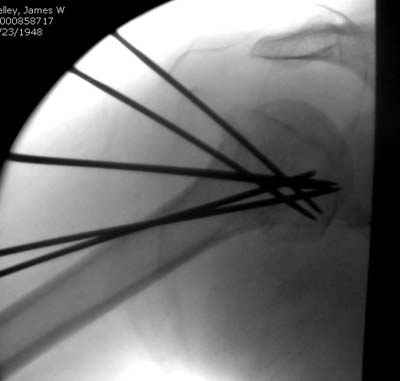

Здесь случай перелома-вывиха плеча, больному 56 лет, после "дважды" закрытой неудачной репозиции, опять же ургентно взяли в операционную, после полного общего обезболивания попытались сделать репозицию, и фиксацию провели спицами.

Больной находился в повязке, примерно напоминяющей косыночную, рекомендованы движения в локтевом суставе и маятниковые движения в плече, спицы удалены в три недели (были случаи миграции)

Больной амбулаторный, предупрежден на случай осложнения АВН головки.